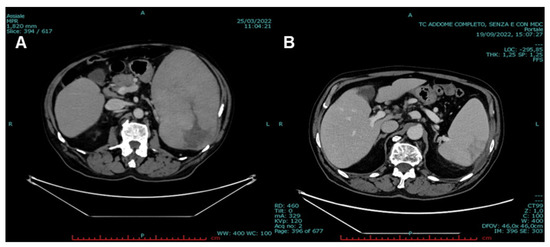

2. Case Presentation